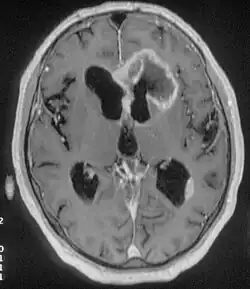

An MRI image of a brain with an invasive, multilocular tumor in the left frontal lobe of the brain.

The origins of frontal lobe seizures can be different deviations.[8] One of the major reasons for FLE is abnormal cognitive development or sometimes congenital abnormal brain development.[8] Other causes are tumors, head trauma, and genetics.[9]

Tumors

Tumors account for about one-third of all frontal lobe epilepsy cases.[9]